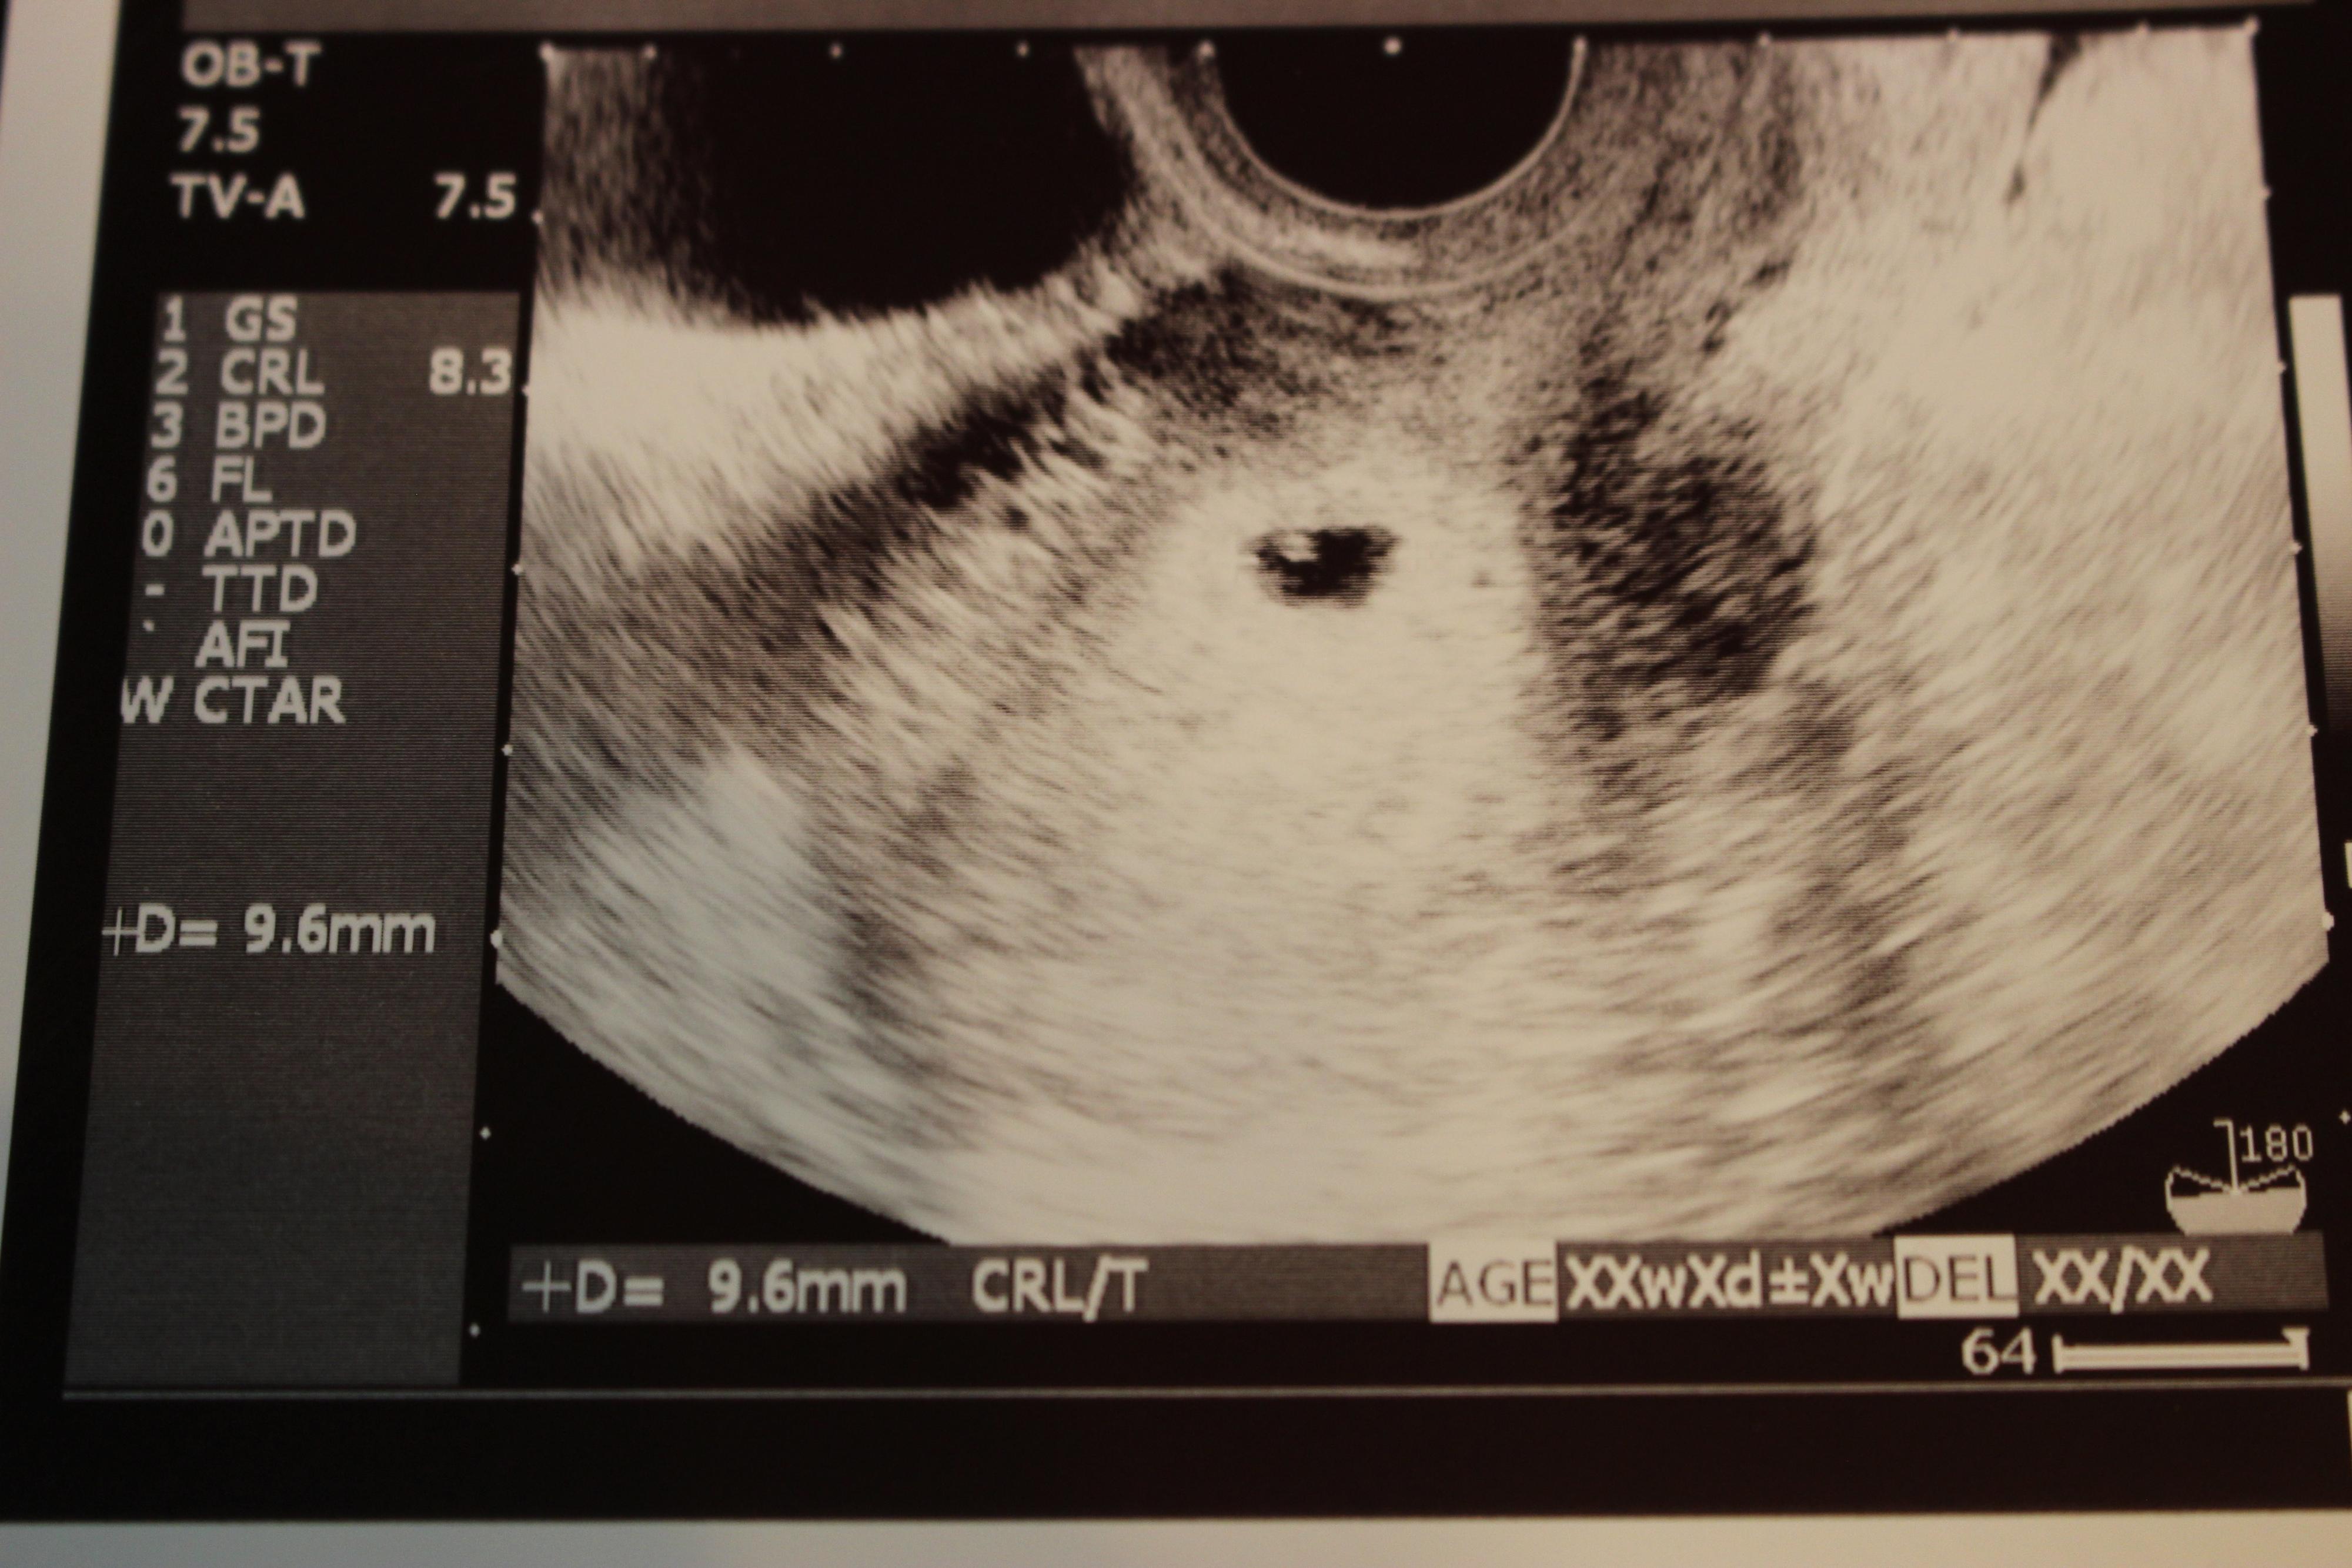

妊娠5週目のエコー写真

妊娠検査薬で陽性反応が出た翌日、病院を受診して最初に撮ったエコー写真です。この時点で妊娠5週目。初めて見る画像でしたが、モニターに映った瞬間「いる!」と胎芽の入っている胎嚢(袋)が確認できました。